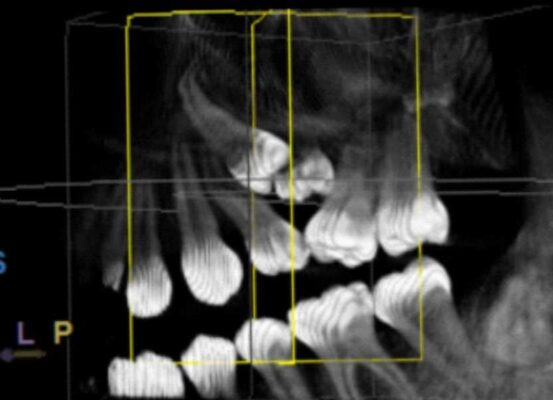

Paciente mujer de 14 años.Derivada de ortodoncia para extracción de un molar temporal retenido y del segundo premolar incluido (no pudo erupcionar por el molar temporal). Afortunadamente el primer pre